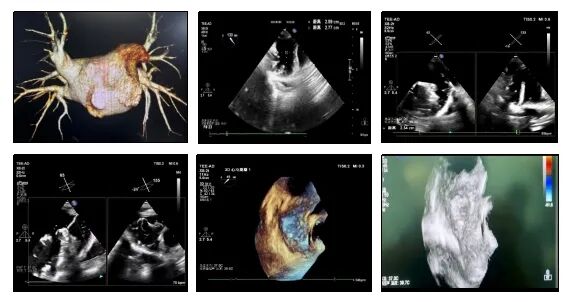

手术精彩过程

术前CT三维重建左心耳开口29mm,深度21mm,从CT上看左心耳开口大,相对有效深度比较浅,但仔细观察发现心耳远端充盈不全,有更多深度,是一个大开口双分叶的左心耳。术中射频消融完成后,对病人进行全麻,放置TEE。TEE不同角度下对患者左心耳进行评估,左心耳开口24-26mm,深度24-27mm,参考术前左心耳CT三维重建,选择33 mm尺寸WATCHMAN左心耳封堵器。通过TEE指引鞘管操作,观察进鞘深度,达到要求后,送输送系统。TEE观察下退鞘展开封堵器,评估满足PASS原则后,释放封堵器。释放后TEE下观察封堵器无位移,患者状况良好

图片